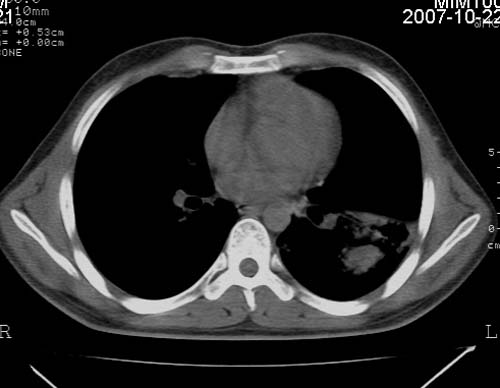

男,21岁,咳嗽、胸闷、乏力伴多汗二十余日、无明显发烧。患者一般情况好,为初三学生。

右肺上叶前段及左肺下叶多形性病变伴厚壁空洞,周边示树芽征.左肺下叶不张改变.

考虑;肺结核,不除外左肺下叶支气管内膜结核.

双肺继发性肺结核伴左侧空洞形成!不除外合并霉菌感染!(双肺多发病灶,左侧病灶形成空洞,并空洞内见壁结节。建议改变体位,观察空洞内结节情况,以便排除霉菌感染!)